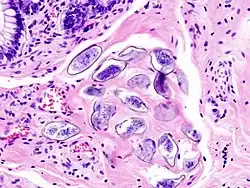

| Obraz histopatologiczny ściany pęcherza zawierającej jaja S. haematobium otoczone tkanką zapalną i naciekiem eozynofilów. | ![]() |

Dorosłe osobniki Schistosoma haematobium żyją w naczyniach żylnych miednicy mniejszej, zwłaszcza pęcherza moczowego, a pozostałe gatunki w żyłach krezkowych. Dlatego patogeneza różni się w postaciach choroby wywoływanych przez S. haematobium i pozostałe gatunki. S. haematobium wywołuje zmiany krwotoczne i zapalne, a potem przerostowe i brodawczakowe ściany pęcherza moczowego i innych narządów miednicy mniejszej; pozostałe gatunki powodują zmiany krwotoczne i wrzodziejące, a następnie polipowate lub bliznowate błony śluzowej jelita cienkiego i grubego. Większość objawów klinicznych ma związek z umiejscowieniem jaj pasożytów w wątrobie, rzadko w płucach.